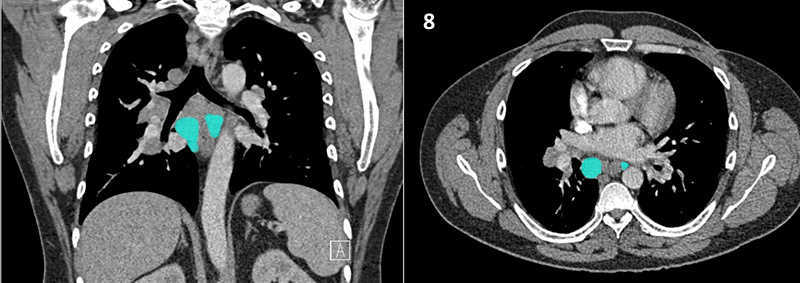

Nodal zones and stations according to the International Association for the Study of Lung Cancer (IASLC) node map.

Table (above): Nodal zones and stations according to the International Association for the Study of Lung Cancer (IASLC) node map. (Source: 1,2) *Depends on the side of the tumour.